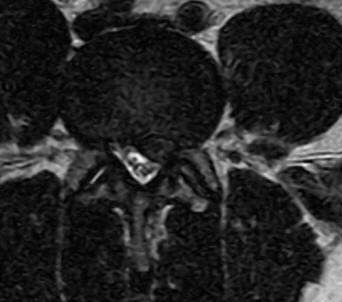

21-DECEMBER-2016  JAAFAR MUHAMED MISLEH 43 YEARS  HUGE EXTRUDED DISK L4-5 WITH LEFT FORAMINAL OCCLUSION.

The patient came to the clinic 20-December-2016 complaining of LBP for 20 years with left sciatica for 2 months with numbness of all toes left foot. MRI lumbar spine performed 14-December-2016 showing huge extruded disc L4-5 with left foraminal occlusion and downward migration. The patient tried all alternative methods of treatment and failed.

The extruded disc L4-5  in sagittal and axial views.